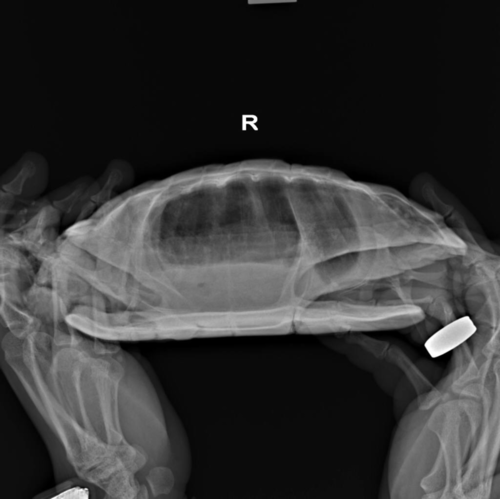

По Воронежу есть информация только о такой клинике, что там могут помочь с черепахой, но на сколько грамотно не могу сказать. В Вашем случае без рентгена в трёх проекциях (или хотя бы в двух) это только гадать пальцем в небо

проекции нужны такие:

обязательно все, что бы там врачи местные не говорили, что это лишнее, что это не нужно и т.п. Это нужно и важно. Только так можно понять состояние лёгких, желудка, репродуктивной системы.

image.thumb.png.3a4129906099ee4692c006bc72e35565.pngimage.thumb.png.ad41f603fd9e257d920b04a60bea2beb.pngimage.thumb.png.2219b5f6e7ddcecb43769ee7fe07e05c.png